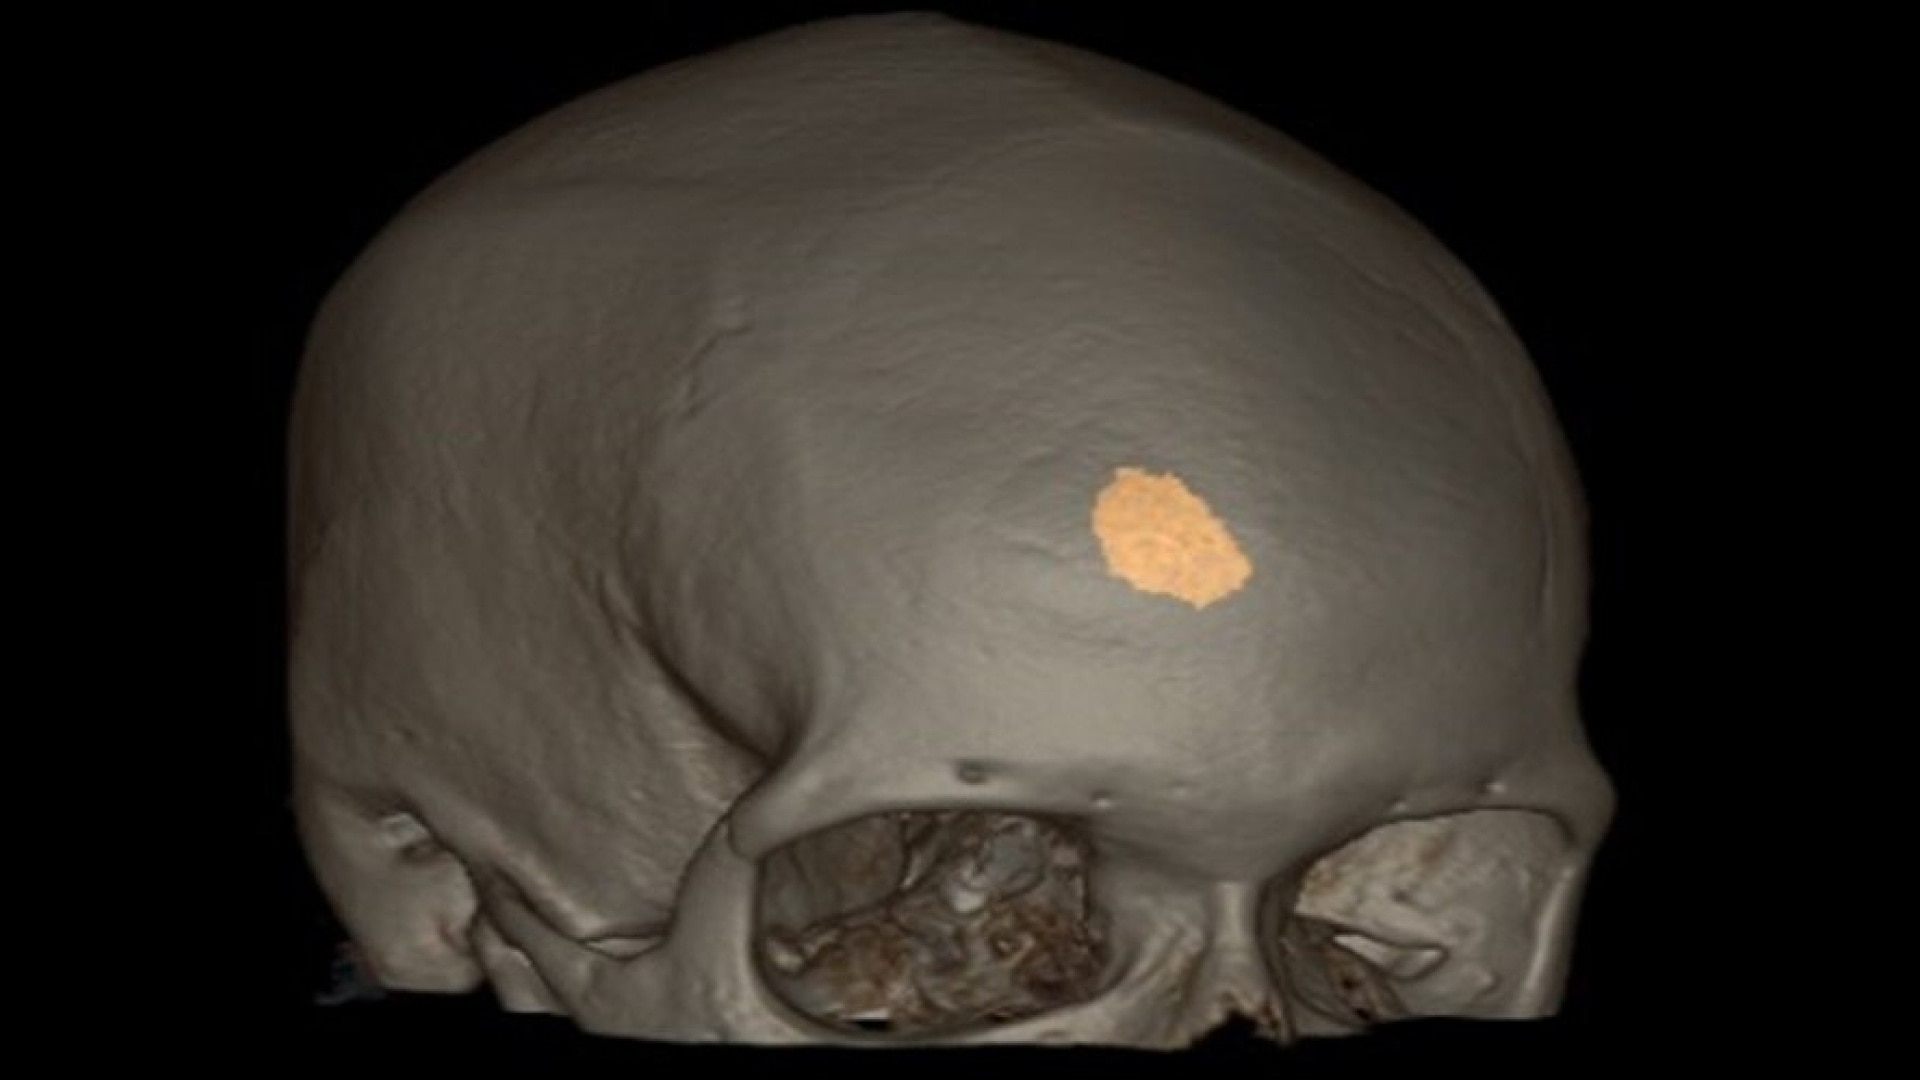

Hematoma

Semi-automated segmentation and sizing of hematoma.

• Semi-automated segmentation and sizing of hematoma

• SmartMesh—an interactive volumetric editing tool

• Track hematoma changes both visually and quantitatively with longitudinal exam workflow